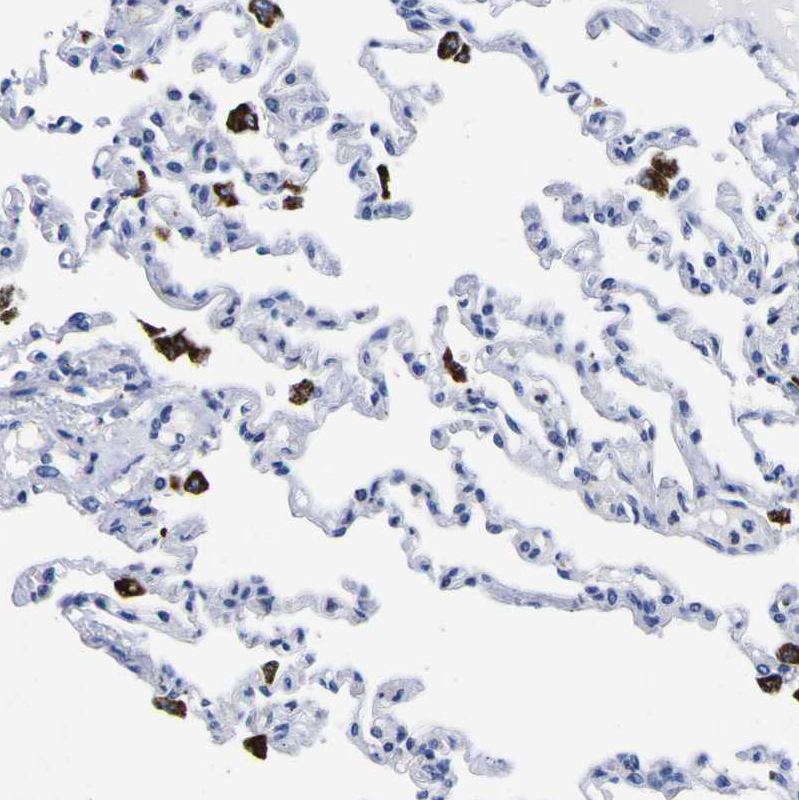

Immunohistochemistry analysis in human tonsil and skeletal muscle tissues using HPA012315 antibody. Corresponding HLA-DQA1 RNA-seq data are presented for the same tissues.